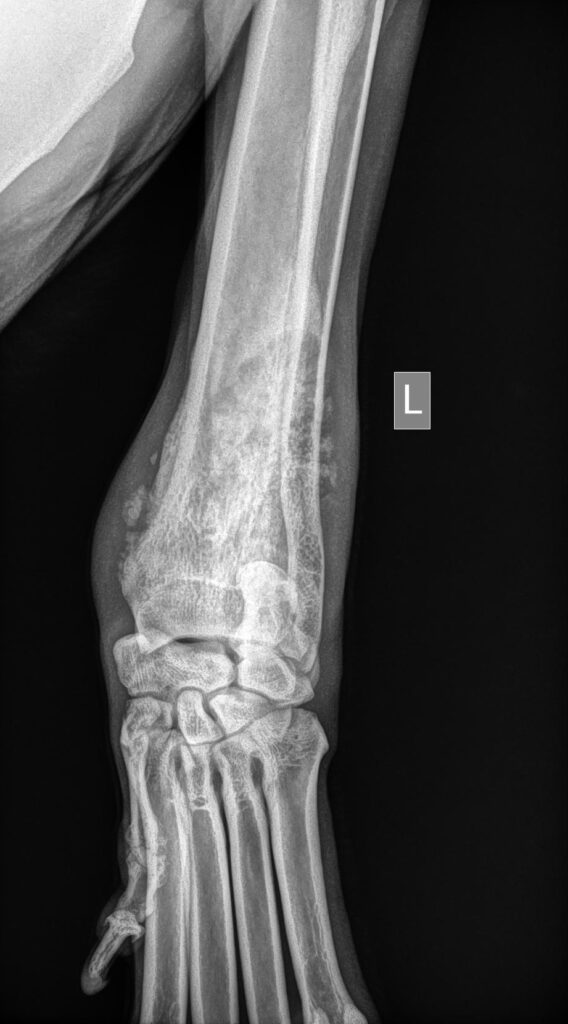

Bij deze hond hebben we ook een uitgebreid lichamelijk onderzoek gedaan. Wat opviel was een flinke zwelling net boven de pols van de linker voorpoot. De pols wordt in de volksmond ook wel de “voorknie” genoemd. Deze term is dus eigenlijk niet juist als je bovenstaande net gelezen hebt. De zwelling was zeer gevoelig bij de aanraking. Het buigen en strekken van de pols was pijnlijk. De rest van de poot liet geen afwijkingen zien. Op basis van deze bevindingen is besloten om röntgenfoto’s te maken van de desbetreffende regio.

We maken minimaal twee foto’s per regio. We doen dit om zo een beter beeld te krijgen. Een pootje is een 3D object. Het is dus lastig om alles op een 2D plaatje te krijgen. Door de foto uit meerdere richtingen te maken krijg je meer informatie. We hebben ook bij deze hond de foto uit twee richtingen genomen. De AP en de ML. Deze termen geven aan dat de eerste foto van boven naar beneden geschoten is, terwijl de tweede foto van binnen naar buiten geschoten is.

- Is de foto correct genomen en hebben we de juiste poot bekeken. We zetten altijd een L of en R op de foto zodat we later terug kunnen zien om welk pootje het ging.

Bij de foto’s van deze hond zien we rondom het uiteinde van het spaakbeen geen mooie botbelijning en we zien een soort woekering. Ook zien we lichte en donkere plekjes in het bot. Omdat deze woekering kan duiden op een bottumor is besloten om ook röntgenfoto’s te maken van de longen om te kijken of er al uitzaaiingen te zien waren. Gelukkig waren deze (nog) niet zichtbaar.